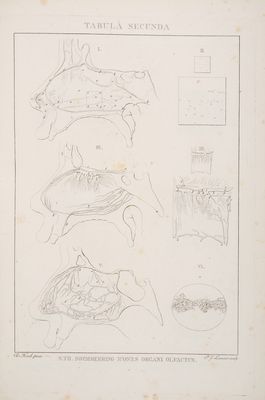

Abbildungen der menschlichen Organe des Geruches / [Von] Samuel Thomas Soemmerring.

- Samuel Thomas von Sömmerring

- 1809

Credit: Abbildungen der menschlichen Organe des Geruches / [Von] Samuel Thomas Soemmerring. Source: Wellcome Collection.